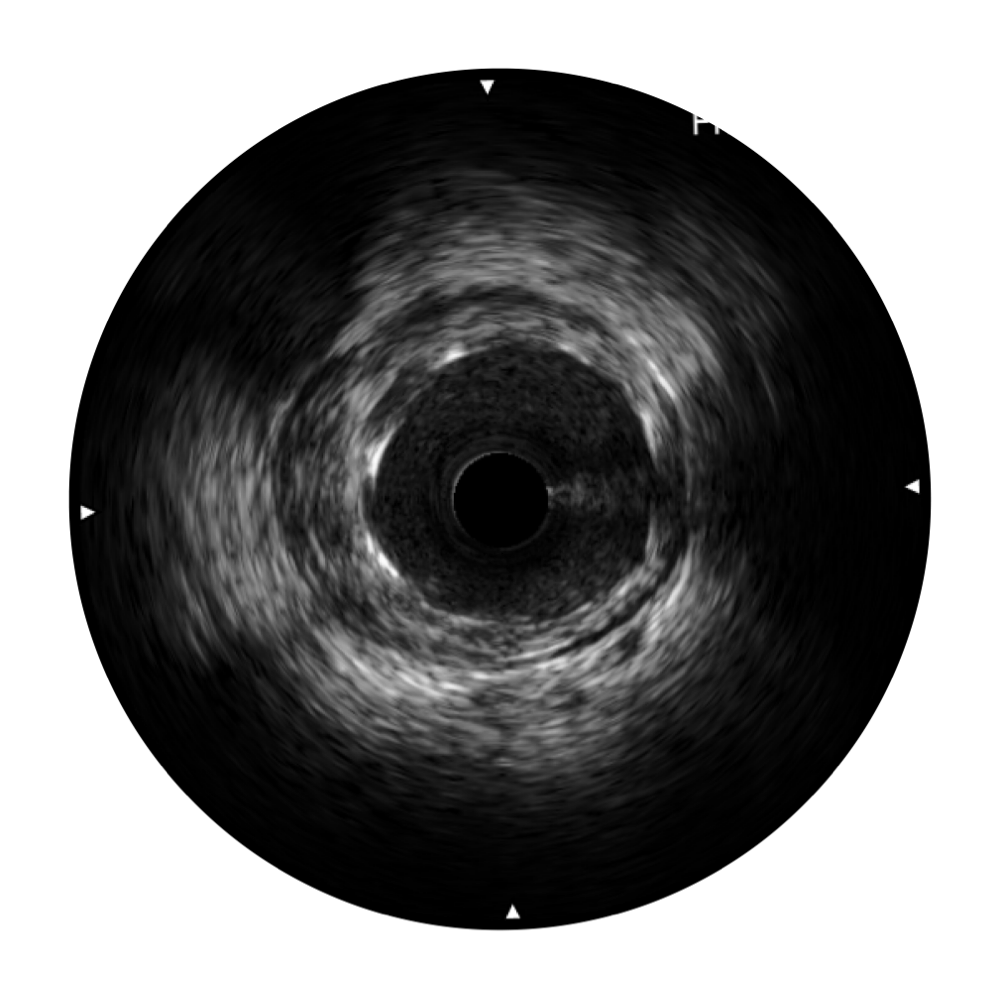

诸侯快讯官网宽频IVUS图像

对比传统IVUS导管成像,诸侯快讯官网宽频IVUS图像的近场支架梁显影更细腻,远场中膜外血管仍清晰可辨,兼顾远中近,兼顾分辨力与穿透深度